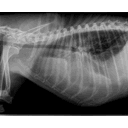

thorax latéral.png